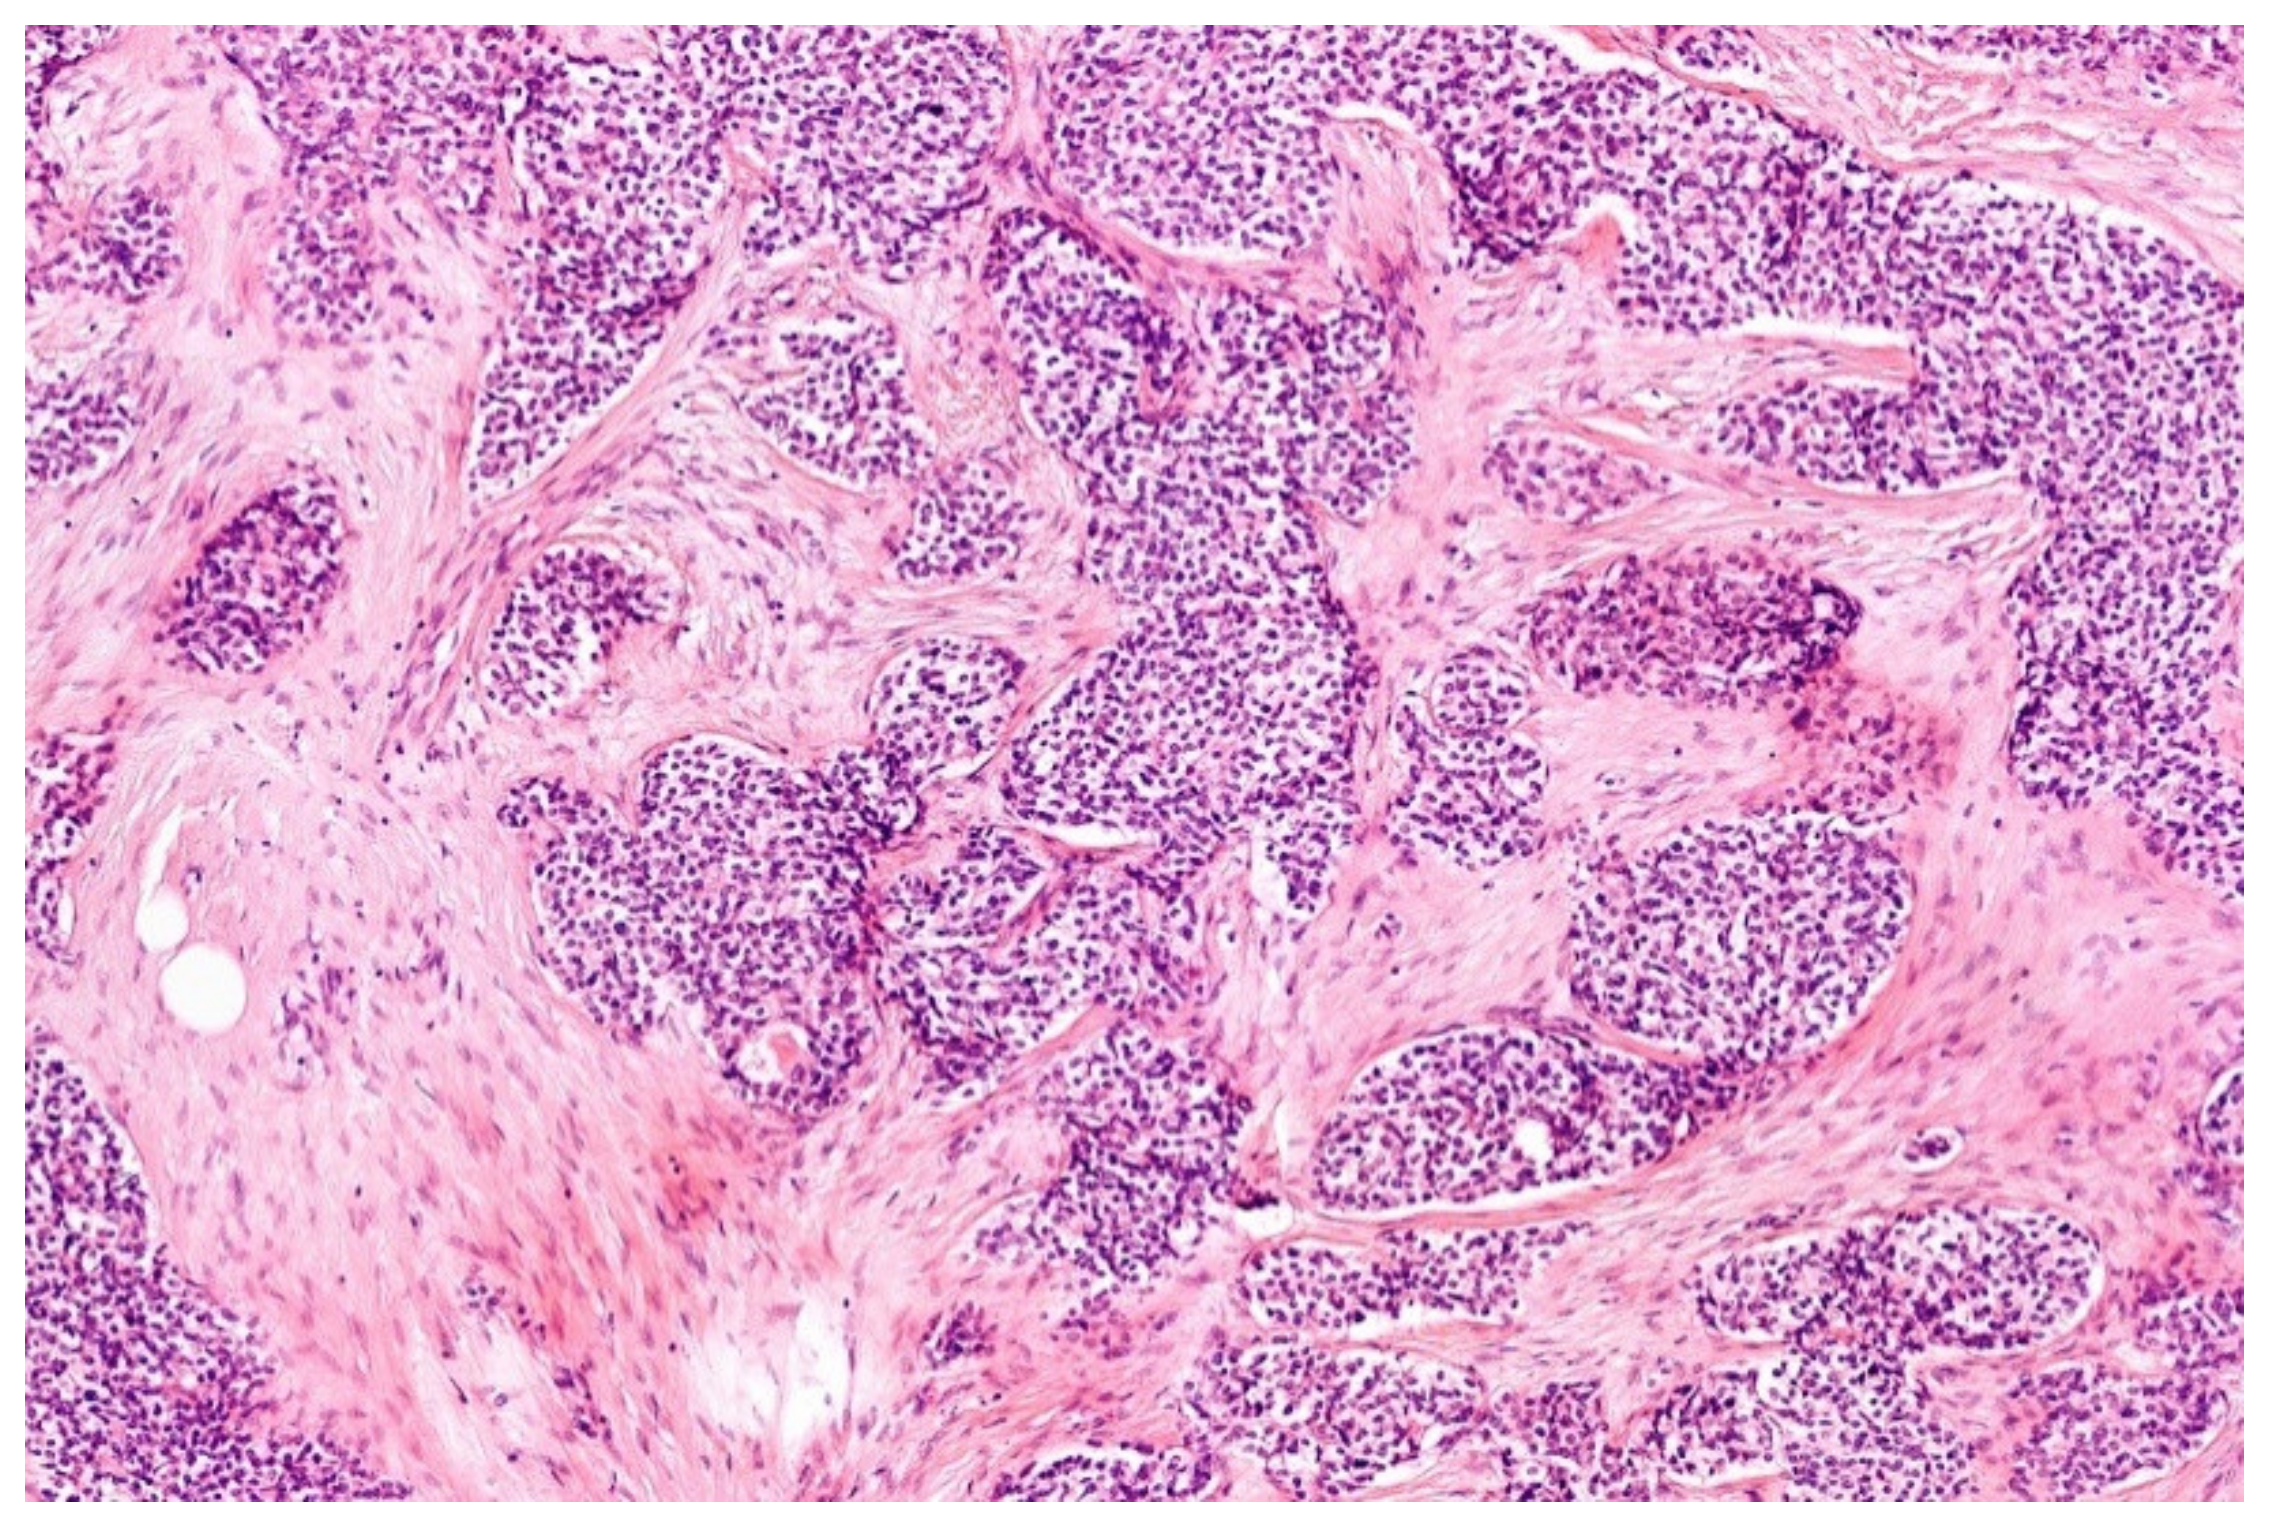

3.4. Desmoplastic Small Round-Cell Tumor (DSCRT)